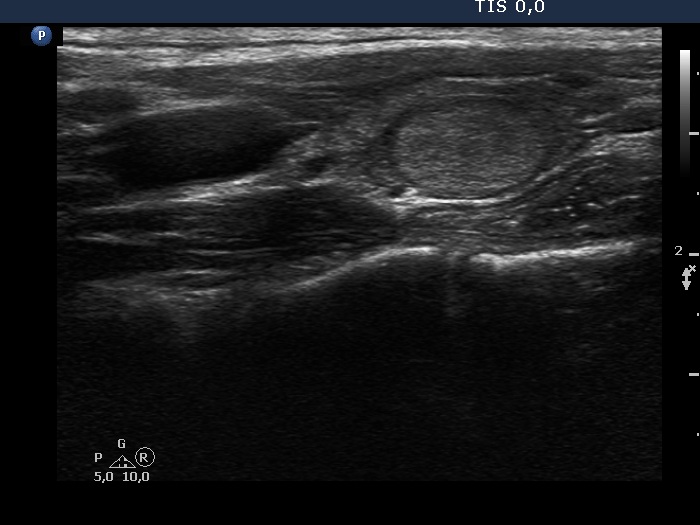

Thyroid cancers - case 2221 (ultrasonographic picture 6)

Left lobe, another longitudinal scan.